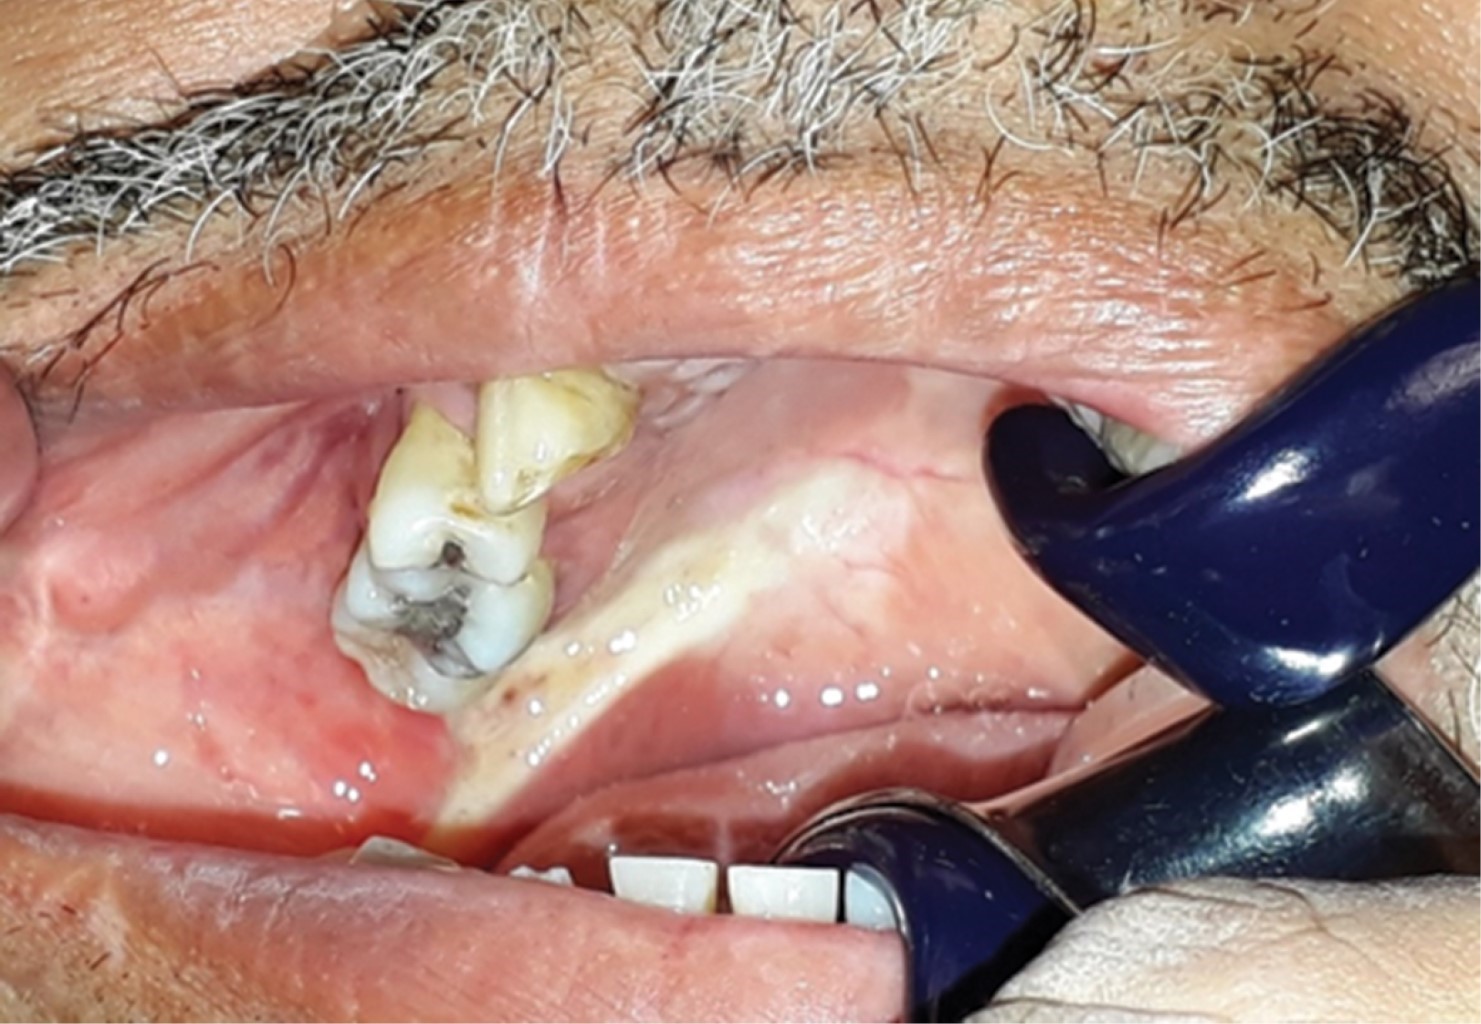

A la exploración clínica se aprecia adecuada simetría facial, perfil recto, sin limitación a la apertura oral. Sin adenomegalias cervicales. Intraoralmente se observa tumoración de 3 × 6 cm de dimensión, localizado en paladar blando que se proyecta a mucosa alveolar inferior retromolar y se extiende a pilar anterior amigdalino del lado derecho, indurado y no dolorosa a la palpación, de coloración violácea, con sangrado al menor estímulo, presenta área de necrosis tisular en el extremo derecho de la tumoración (Figura 1). El resto de la mucosa bien hidratada de color y consistencia normal, anodoncia parcial, prótesis fija metálica anterosuperior desajustada, mala higiene.

Figura 1